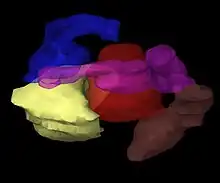

Creation of a virtual patient

The images of the patient with the applicators in situ are imported into treatment planning software and the patient is brought into a dedicated shielded room for treatment. The treatment planning software enables multiple 2D images of the treatment site to be translated into a 3D 'virtual patient', within which the position of the applicators can be defined.[1]: Ch. 5 The spatial relationships between the applicators, the treatment site and the surrounding healthy tissues within this 'virtual patient' are a copy of the relationships in the actual patient.

Optimizing the irradiation plan

To identify the optimal spatial and temporal distribution of radiation sources within the applicators of the implanted tissue or cavity, the treatment planning software allows virtual radiation sources to be placed within the virtual patient. The software shows a graphical representation of the distribution of the irradiation. This serves as a guide for the brachytherapy team to refine the distribution of the sources and provide a treatment plan that is optimally tailored to the anatomy of each patient before actual delivery of the irradiation begins.[85] This approach is sometimes called 'dose-painting'.